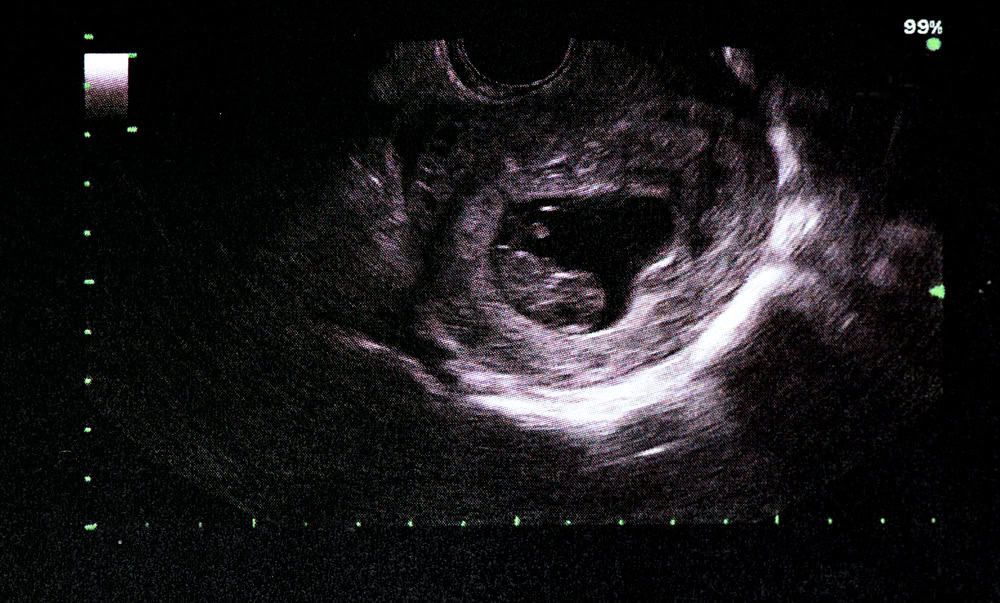

- Các bộ phận trên gương mặt: Chóp mũi nhỏ xíu và chiếc miệng nhỏ lúc này đã phát triển và có thể được nhìn thấy trong phim chụp khi siêu âm.

- Da trên mắt: Phần da trên mắt bé cũng đang bắt đầu hình thành mí mắt. Mẹ sẽ có thể nhìn thấy mí mắt bé rõ ràng hơn khi đi siêu âm thai trong vài tuần tới.

- Cơ bắp đã phát triển nên bé có thể thực hiện một số cử động đầu tiên trong tuần thai thứ 9. Tuy vậy, mẹ không thể cảm nhận được những cử động ấy của thai nhi 9 tuần một cách trực tiếp qua bụng mà chỉ có thể nhìn thấy khi đi siêu âm mà thôi.

- Siêu âm thai

Để xác định thai nhi 9 tuần có khỏe mạnh, phát triển bình thường hay không, mẹ bầu cần đi khám thai và làm siêu âm để theo dõi sự phát triển của bé yêu. Theo các chuyên gia sức khỏe, những dấu hiệu thai nhi 9 tuần khỏe mạnh có thể kể đến như:

- Khuôn mặt: Chóp mũi và miệng của bé trở nên rõ nét hơn.

- Nhịp tim: Nhịp đập tim thai nhanh gấp đôi người trưởng thành, khoảng 170 lần/phút.